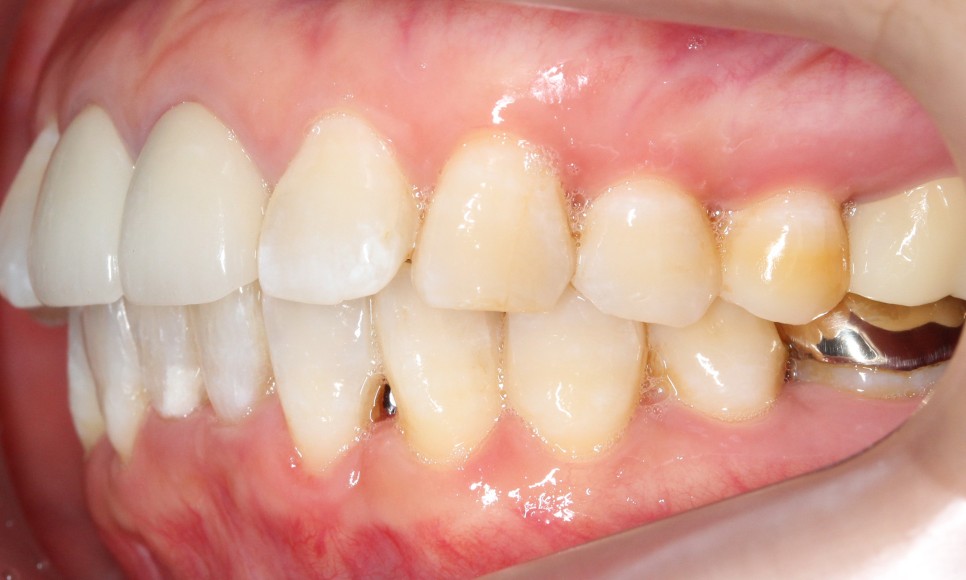

측면을 보시면

아랫니의 앞쪽이 윗니의 뒷쪽으로

많이 들어가 있는 것을

확인할 수 있습니다.

반대쪽으로 보아도

같은 모습을 확인할 수 있는데요.

이렇게 아랫니가 윗니를 향해

깊숙히 물린다면

아랫니의 절단연에 의해

윗니의 잇몸이 상처 입을 수 있습니다.